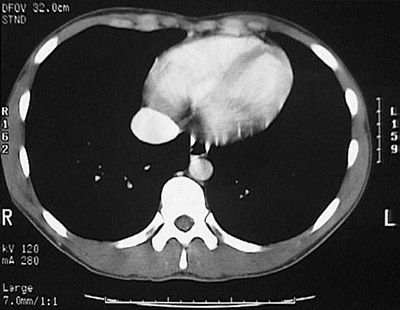

[T9] This is a normal abdominal CT scan with contrast demonstrating the left ventricle and right ventricle and right lung and left lung and vertebral body and vertebral transverse process and vertebral spinous process and spinal canal and rib and aorta in the lower chest.